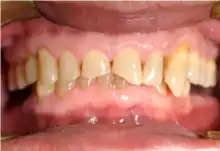

Frontal view of severe tooth erosion in GERD[26]

Severe tooth erosion in GERD[26]

Acid reflux into the mouth can cause breakdown of the enamel, especially on the inside surface of the teeth. A dry mouth, acid or burning sensation in the mouth, bad breath and redness of the palate may occur.[27] Less common symptoms of GERD include difficulty in swallowing, water brash, chronic cough, hoarse voice, nausea and vomiting.[26]

Signs of enamel erosion are the appearance of a smooth, silky-glazed, sometimes dull, enamel surface with the absence of perikymata, together with intact enamel along the gum margin.[28] It will be evident in people with restorations as tooth structure typically dissolves much faster than the restorative material, causing it to seem as if it "stands above" the surrounding tooth structure.[29]